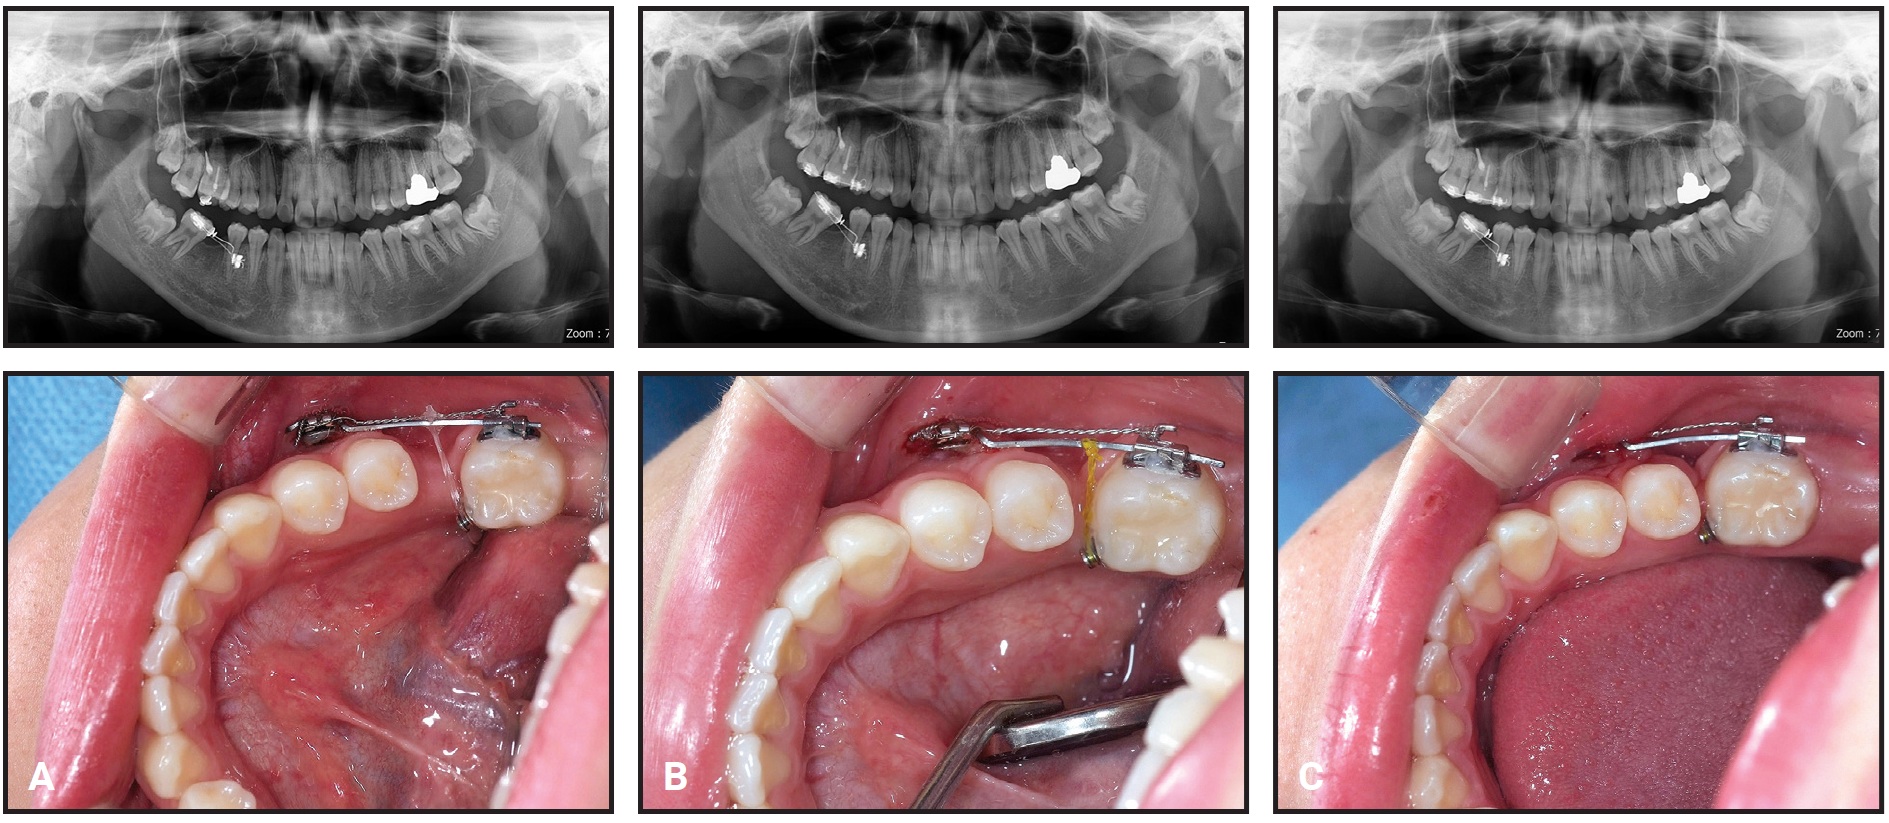

A 16-year-old female scheduled for prosthodontic treatment was referred for intrusion of an overerupted upper right first molar after decay of the lower first molar (Fig. 6).

Fig. 6 Case 2. 16-year-old female patient with extracted lower right first molar and extruded upper right first molar before treatment.

The patient presented with the lower right molar already extracted, so intrusion of the upper right first molar and protraction of the lower right second and third molars were planned.

Two small-headed micro-implants were placed in the buccal (7mm) and palatal (10mm) sides of the upper right posterior area, and an intrusion force was applied to the upper right first molar (Fig. 7).

Fig. 7 Case 2. A. 7mm micro-implant placed in upper right posterior bone on buccal side and 10mm micro-implant on palatal side. B. Intrusion force applied to upper right first molar.

After a modest amount of intrusion had been achieved, protraction of the lower second and third molars was started to close the extraction space with micro-implant anchorage.

After six weeks of treatment, two small-headed 6mm micro-implants were placed into the buccal alveolar bone between the lower right first and second premolars, tied with a stainless steel ligature wire, and built up with composite resin, as in Case 1 (Fig. 8). A standard .018" upper-incisor bracket was bonded to the composite, a tube was bonded to the lower second molar, and an .017" × .025" TMA sectional wire was inserted. Reactivation was performed by tightening the ligature wire every four weeks (Fig. 9).

Fig. 8 Case 2. A. Bracket bonded over two micro-implants between lower right first and second premolars, as in Case 1. B. Mesial force applied with TMA sectional wire.

Fig. 9 Case 2. Mesial tipping of lower right second molar and development of bone atrophy near first-molar extraction space during protraction. A. After six months of treatment. B. After 10 months of treatment. C. After 14 months of treatment.

The intrusion force was applied continuously to the upper right first molar, and the lower second molar was intruded slightly by the sectional archwire to avoid occlusal contact during protraction. Panoramic radiographs indicated forward tipping of the lower second molar rather than bodily movement.